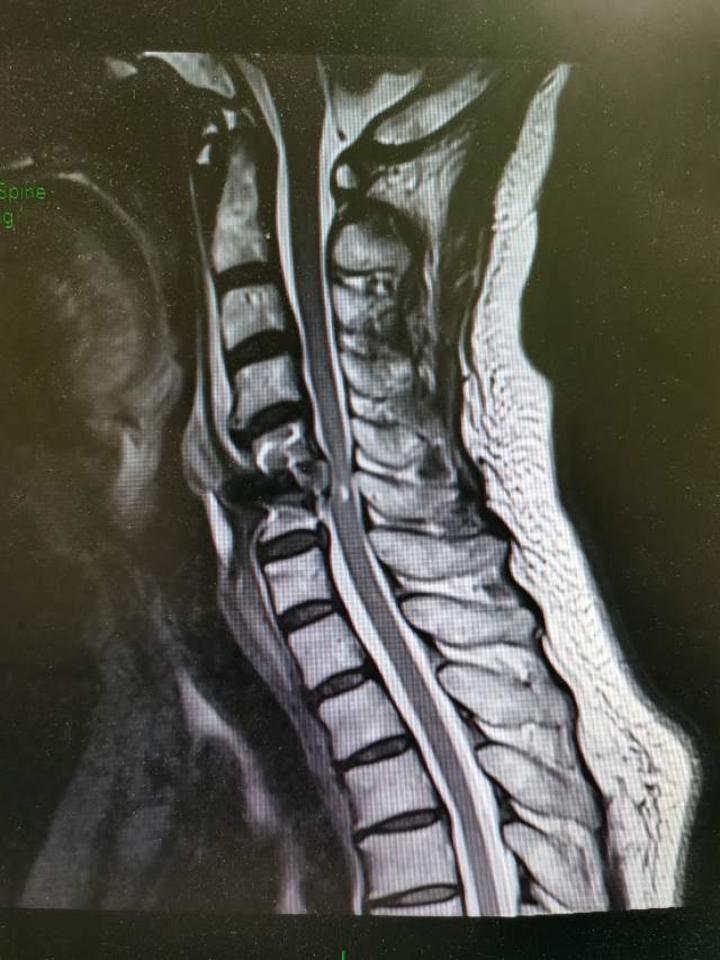

一例严重颈椎后纵韧带骨化症

是由于颈椎椎间盘突出,骨赘增生,后纵韧带骨化,黄韧带增厚等压迫脊髓

颈椎后纵韧带骨化症